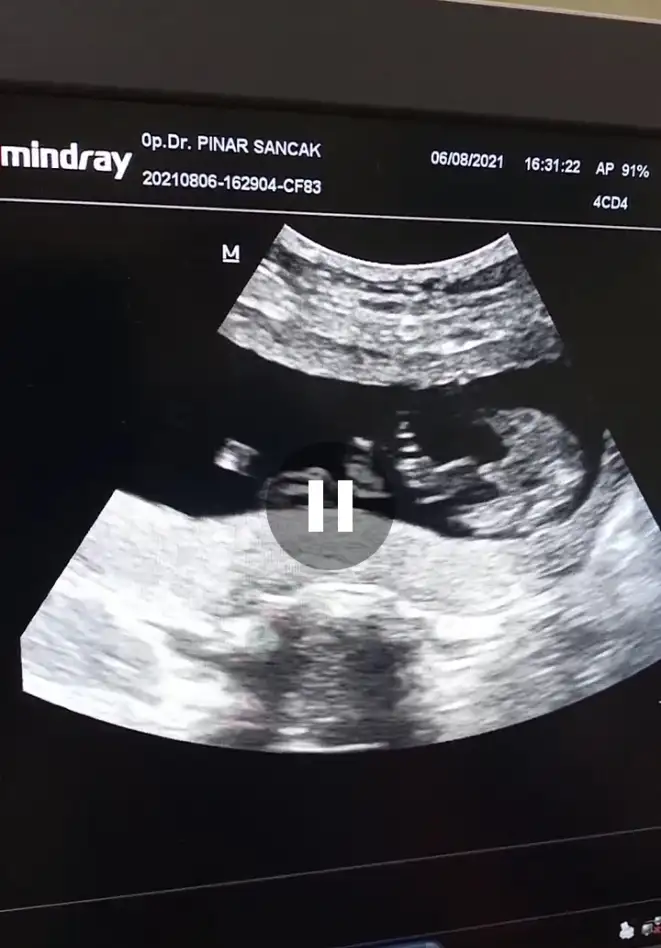

Erkek gibi sanki emin olamadım en iyi 11 12 13 haftalarEki Görüntüle 2896935 merhabalar tahmininizi alabilir miyim. SAT a göre 13+1 usg de 14 çıktı

Erkek sanki emin olamadımIkra meyra İki farklı doktor kız dedi bugün 16 haftalık bacak arası fotosu dr erkek olduğu nu söyledi o bacak arasındaki pipimi doktor öyle dedi sizin de fikrinizi alabilir miyim

Erkek sanki emin olamadım